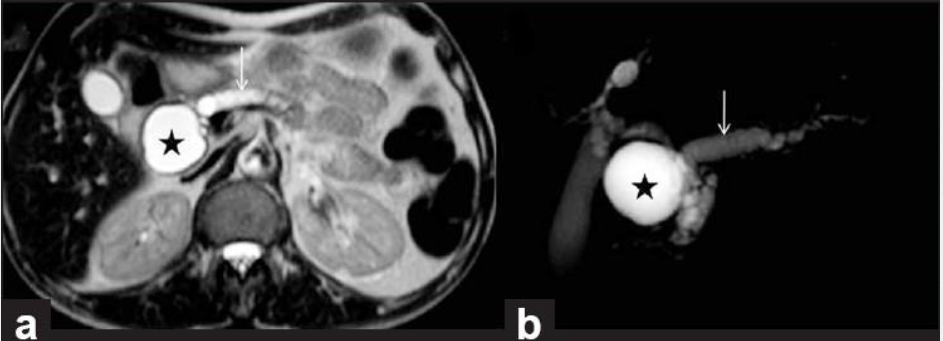

Q

מהו הממצא

A

ציסט-אדנוקרצינומה

How well did you know this?